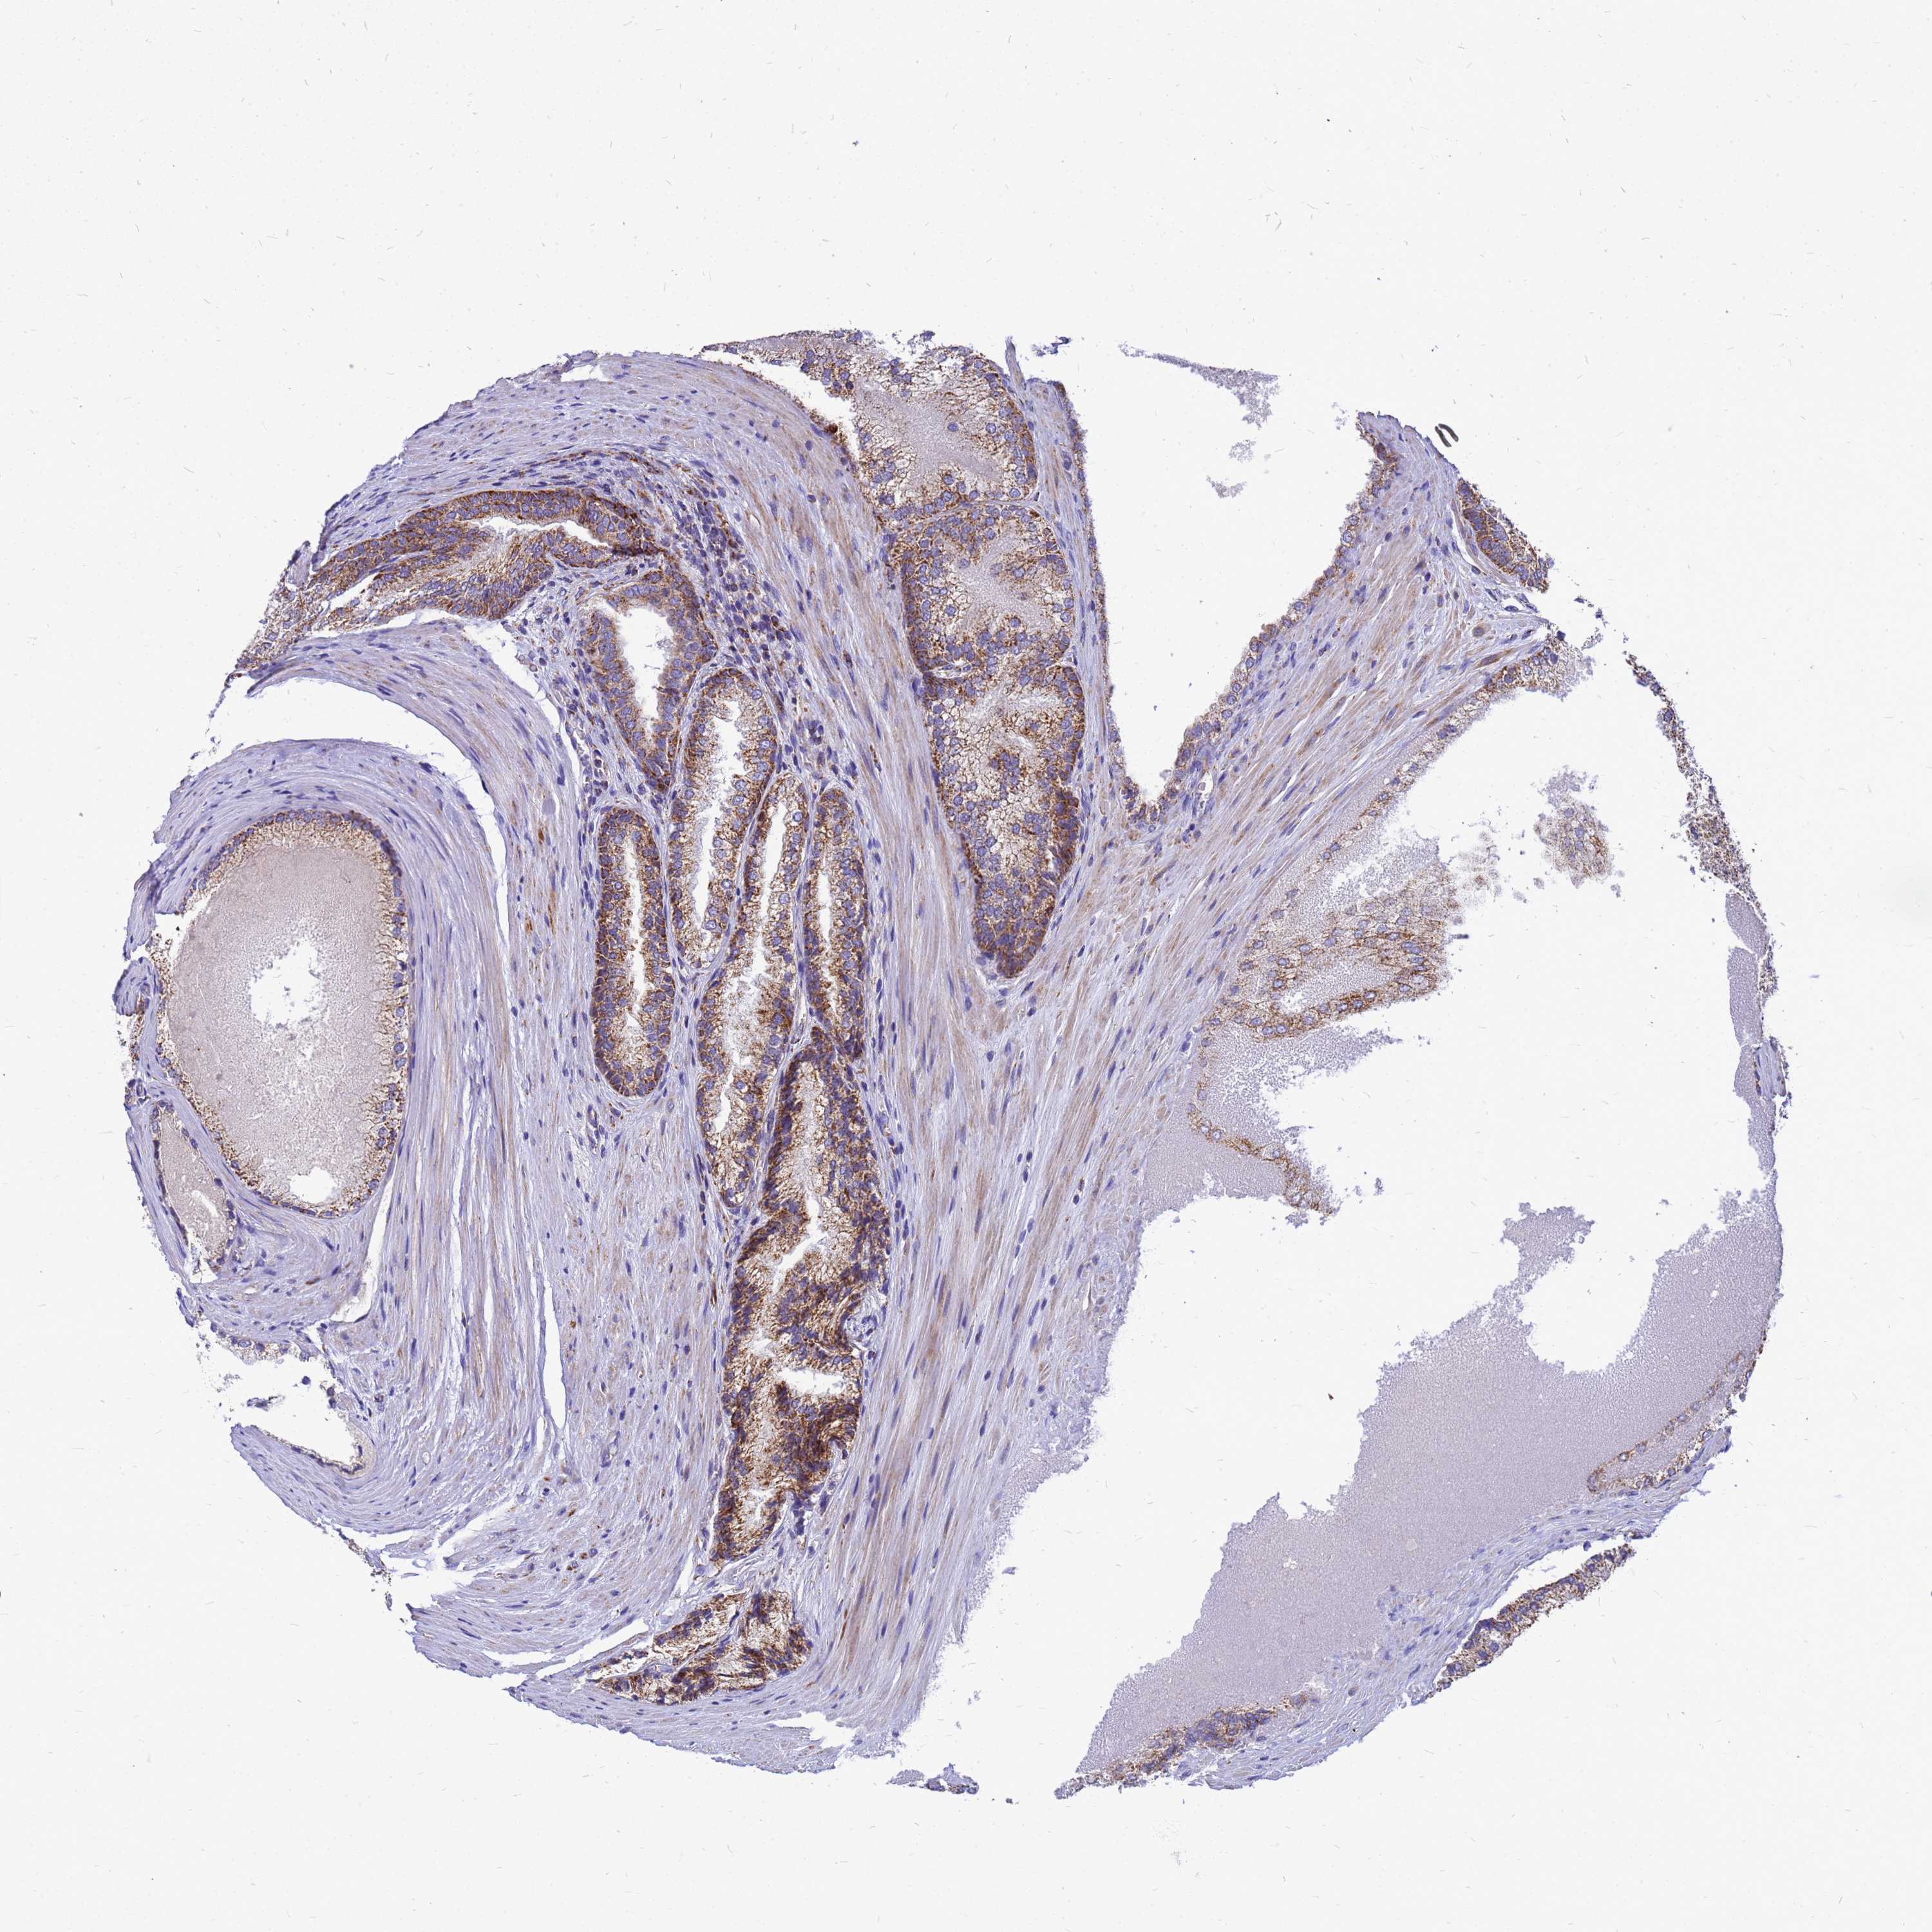

PROSTATE CANCER - Protein expressioni

A mouse-over function shows sample information and annotation data. Click on an image to view it in a full screen mode. Samples can be filtered based on level of antibody staining by selecting one or several of the following categories: high, medium, low and not detected. The assay and annotation is described here.

Note that samples used for immunohistochemistry by the Human Protein Atlas do not correspond to samples in the TCGA dataset.

Antibody stainingi

Antibody staining in the annotated cell types in the current human tissue is reported as not detected, low, medium, or high, based on conventional immunohistochemistry profiling in selected tissues. This score is based on the combination of the staining intensity and fraction of stained cells.

Each image is clickable and will lead to virtual microscopy that enables deeper exploration of all samples and also displays staining intensity scores, fraction scores and subcellular localization as well as patient and tissue information for each sample.

Antibody HPA045866

Staining

High

Medium

Low

Not detected

Intensity

Strong

Moderate

Weak

Negative

Quantity

>75%

75%-25%

<25%

None

Location

Nuclear

Cytoplasmic/membranous

Cytoplasmic/membranous,nuclear

Adenocarcinoma, NOS

Adenocarcinoma, High grade

Adenocarcinoma, Low grade